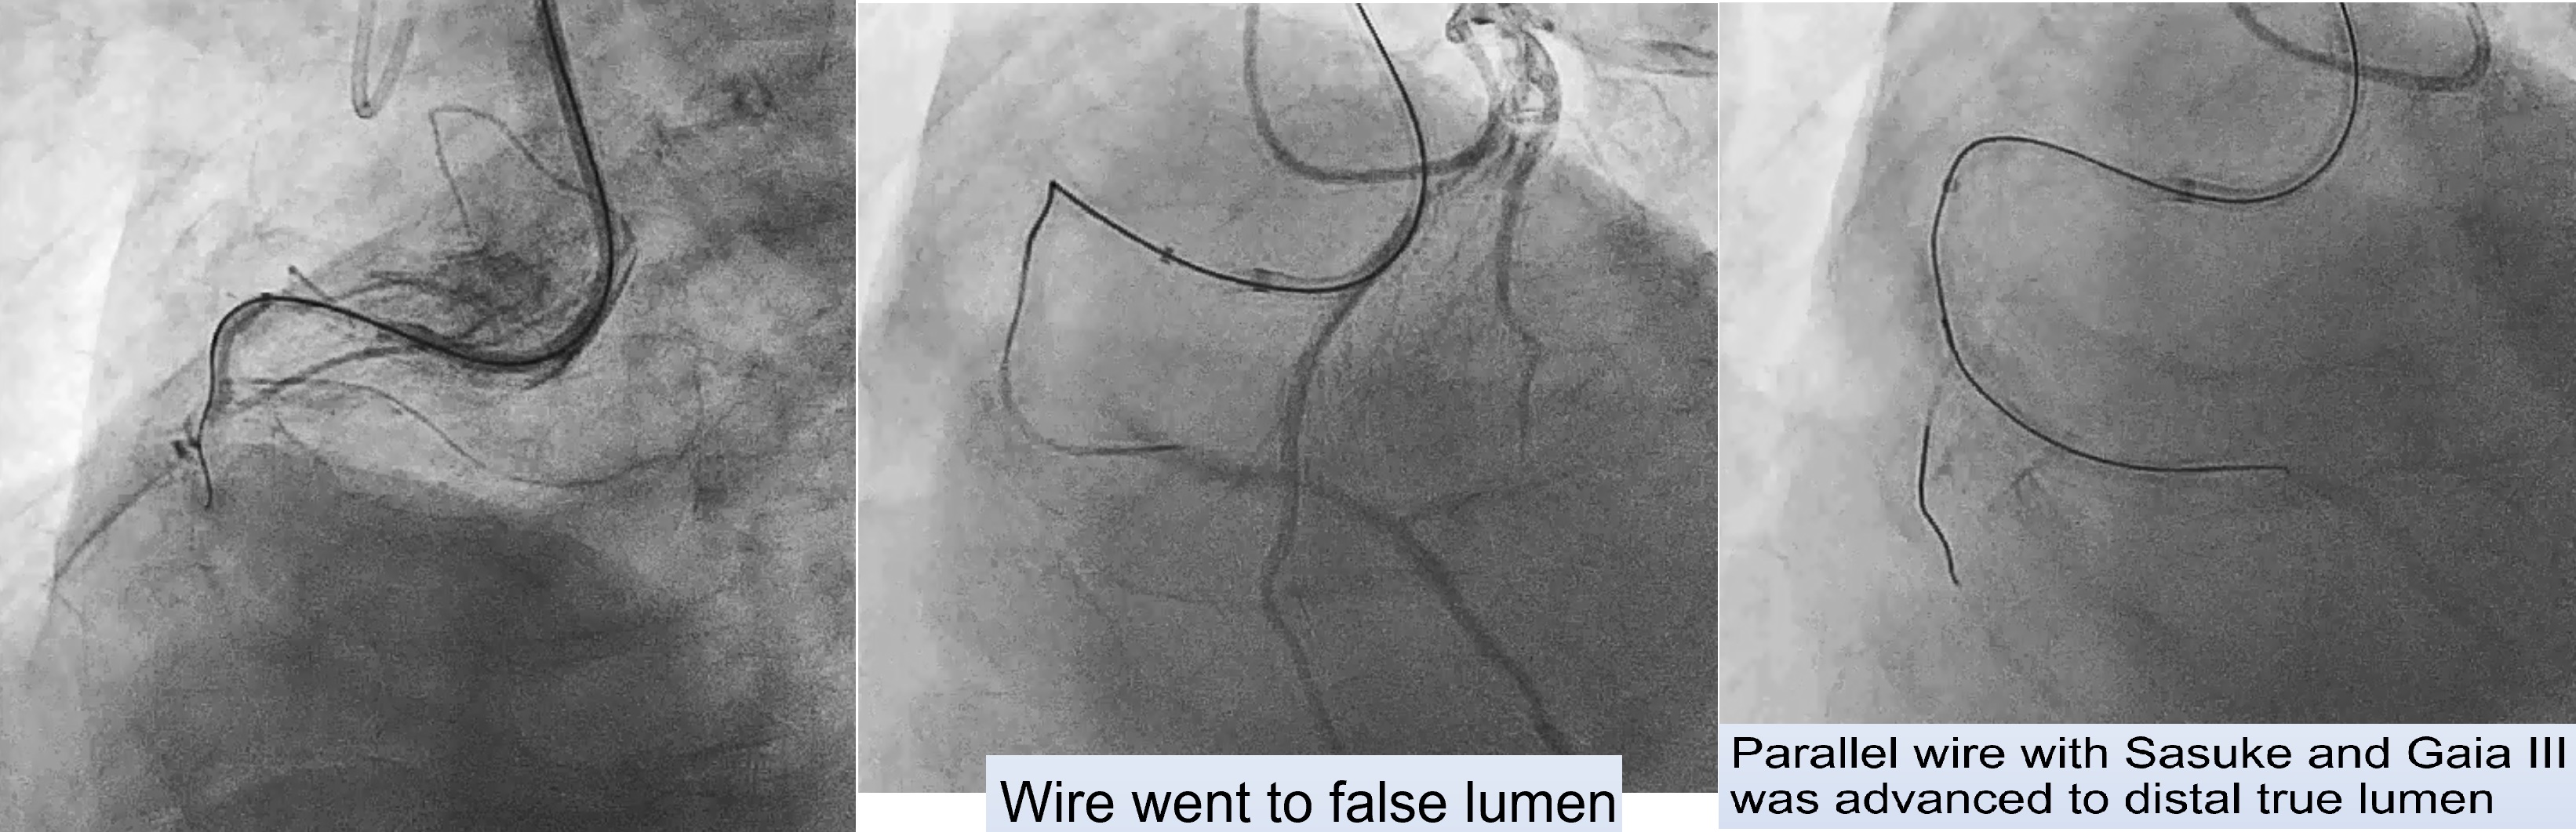

First Procedure: An antegrade approach was initially attempted with wire escalation strategies (using XTA, Fielder FC, Gaia I, II, III, Conquest pro in Cosair), but the wire entered a false lumen. Shift to parallel wire technique with Sasuke. The Gaia III wire eventually reached the distal true lumen. Balloon dilation was attempted, but the CTO segment remained undilatable. IVUS confirmed severe calcification, so a 1.25 mm rotational atherectomy (ROTA) burr was used, which led to mild improvement but still left an undilatable lesion. The procedure was paused because the patient could not tolerate lying flat for an extended time.Second Procedure was performed 3 months later. RCA still showed stenosis despite receiving collateral flow from LAD. Balloon dilation attempts were unsuccessful, necessitating a shift to a 1.75 mm ROTA burr for further plaque modification.After successful lesion modification, further preparation for stenting was performed, followed by the deployment of a 3.0 x 48 mm and a 3.5 x 48 mm drug-eluting stent (DES) in the RCA. Final IVUS confirmed adequate stent placement with good distal runoff. Additional stenting was performed in the LCx and LAD.

Case Summary

For patients who cannot tolerate prolonged procedures, particularly in complex CTO cases, a staged approach utilizing rotational atherectomy followed by drug-eluting balloon (DEB) application can be effective. The DEB provides interim drug delivery, reducing restenosis risk and allowing time for the patient to recover before the next procedure. This approach is especially beneficial for high-risk patients needing multiple sessions for complete revascularization.